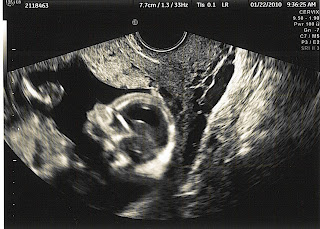

• Mine was really big, this is a picture of it from like 16/18wks?  All the black on the right by her head is the SCH.  It cleared by 24wks completely.

• Yeah, mine is tiny compared to that. Did you get more frequent ultrasounds because of it?